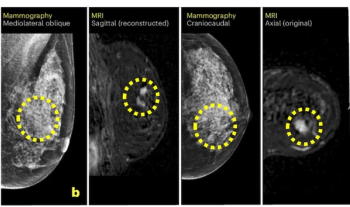

The combination of mammography with breast MRI within 90 days had a 96.2 percent sensitivity in comparison to 48.1 percent for mammography and 79.7 percent for breast MRI performed within 91 to 270 days after index mammography, according to newly published research.